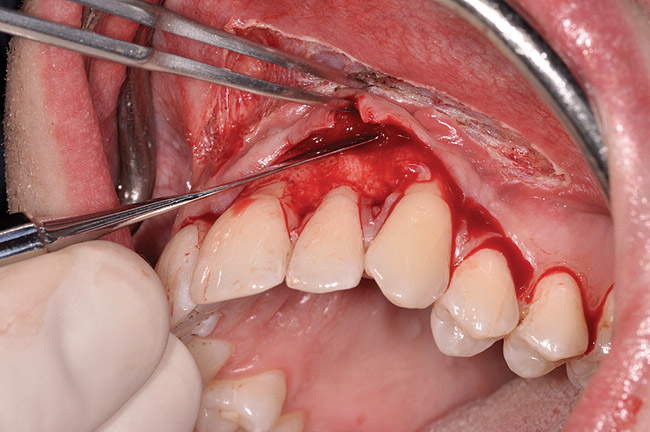

After initial incision techniques were done, a papillary-sparing incision was performed, leaving the crest of the papilla intact (Figure 10), thus allowing flap closure to be accomplished with a bed of autogenous tissue to support revascularization of the dermis/buccal flap complex. A full-thickness flap was then elevated to the mucogingival junction, after which a split-thickness dissection with a blunt elevator superior to the mucogingival junction area was performed to allow for release of tension and to let the buccal flap be mobilized coronally at closure (Figure 10). Care must be taken to avoid perforating the tissue in the region of the vestibuloplasty incision. After tension-free release of the flap, root planing of the exposed root surfaces was accomplished, followed by removal of the smear layer of cementum and chemical detoxification with a citric acid solution pH1 applied over the previously root-planed surfaces. After root preparation, the keratinized papillary tissues that remained following initial incisions were de-keratinized by using a #4 round diamond on a high-speed handpiece. De-keratinization provided a wound bed that enabled the dermal matrix graft to be secured and supported revascularization of the coronally repositioned buccal flap at closure.

Fig 10. Initial incisions, and blunt, split-thickness dissection for tension-free closure.

Figure 10